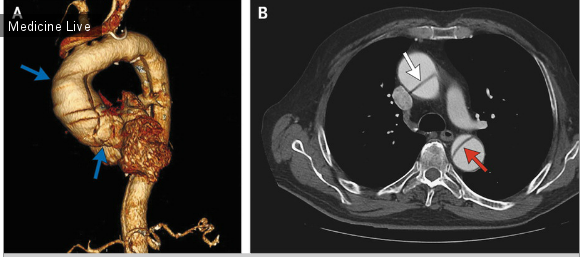

Бурденко аневризма

Бурденко аневризма 107 фото